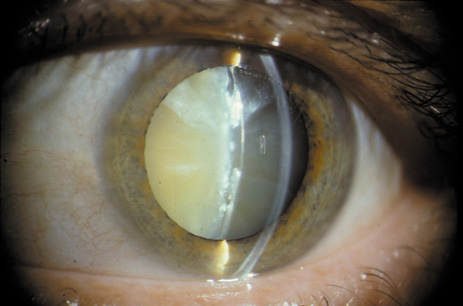

One can examine this type of cataract with direct illumination, using the narrow and broad beams of the slit-lamp to show the characteristic granular inner surface immediately in front of the posterior capsule (Fig. 13). The problem with this technique, however, is that patients may not tolerate any prolonged direct illumination because of the glare. Retroillumination is therefore more useful for revealing the outline of the opacity, since it is usually seen as an “island” in the center of the posterior capsule, which is further highlighted by the shadow cast by the opacities.33 However, in the early stages of this type of cataract, the dust-like particles that might be noticeable in the central posterior subcapsular area with direct illumination disappear or are difficult to see with retroillumination (Fig. 14). Eventually this “dusting” becomes dense enough to cast a shadow and thus appear on retroillumination. The smooth orange background of the fundus helps to highlight the rough, irregular pseudopodia-like edges of the central opacity. In advanced stages, the PSC may become a thick, calcified plaque (Fig. 15). During surgery, excessively vigorous scraping or vacuuming of the calcified opacity can lead to rupture of the posterior capsule. Usually, small remnants that are left behind after surgery are reabsorbed and do not interfere with vision; otherwise, they are easily treated with a neodymium : yttrium (Nd:YAG) aluminum garnet laser. Pathologic evidence suggests that most PSCs result from the migration of bow region cells into the potential space (along with accumulated cellular debris) between the posterior capsule and the cortex.34–36

Fig. 15. Example of an Oxford camera retroillumination image of a PSC, and the automated method used to measure the area of cataract.